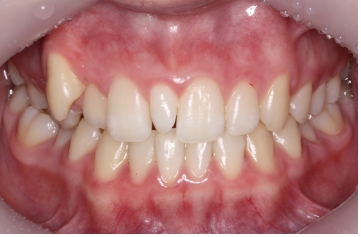

ÀÌ·± °æ¿ì °úÀ×Ä¡¸¦ ¹ßÄ¡ÇÏ°í °£´ÜÇÑ ±³Á¤Ä¡·á·Î ¹®Á¦¸¦ ÇØ°áÇØÁÙ ¼ö ÀÖ½À´Ï´Ù.

°úÀ×Ä¡¸¦ ¹ßÄ¡ÇÑ ÈÄ¿¡ ±³Á¤Ä¡·á¸¦ ÅëÇØ ¹®Á¦¸¦ ÇØ°áÇØÁÖ¾ú½À´Ï´Ù.